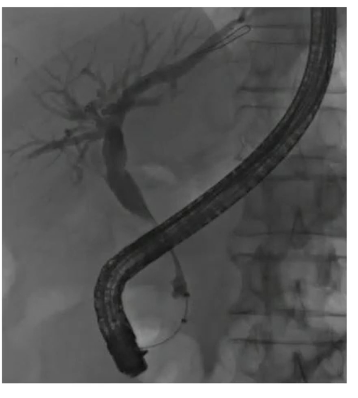

Aortoentertic fistula